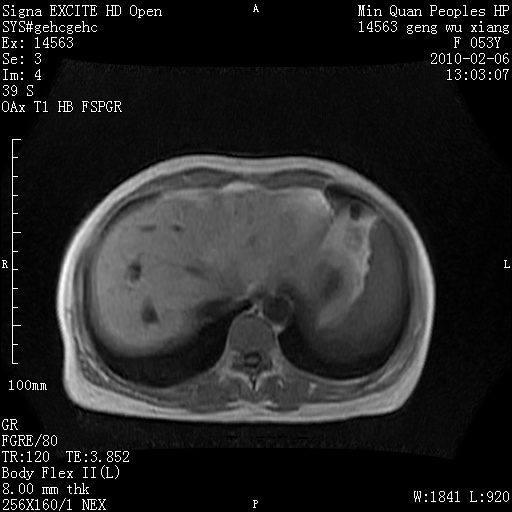

标题: MRI2762:胆道梗阻原因?

f,53y,全身黄染多日。

高位胆道梗阻 胆管癌可能性大

支持 高位胆道梗阻 胆管癌可能性大。